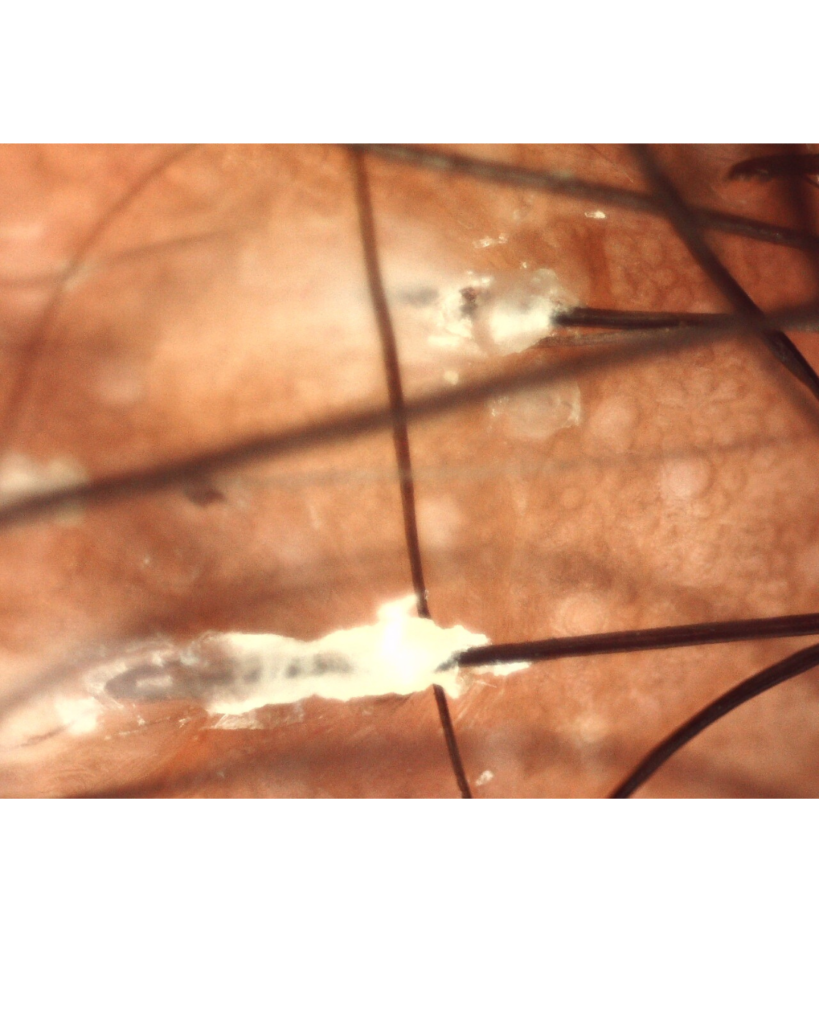

Abaixo vemos duas imagens de tricoscopia em cabelo cacheado com alopecia por tração.

A avaliação com tricoscopia ou dermatoscopia pode auxiliar no diagnóstico diferencial. Um profissional Dermatologista , Tricologista ou um técnico em Terapia Capilar podem te auxiliar a identificar e tratar os sinais da alopecia por tração. A detecção precoce é decisiva para a reversão.